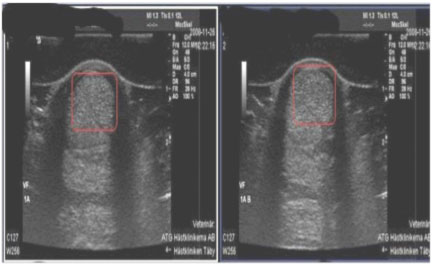

Example 1: 11-year-old quarter horse

History: Moderate tear of the medial collateral ligament of the right front coffin joint.

Left image: Sonogram of medial collateral ligament of right front coffin joint, showing enlarged cross-sectional area and a fresh-appearing core lesion.

Ultrasound Impressions: Image on the right was taken 3 months after image on the left and according to the veterinarian it shows reduced effusion and reduced synovitis in comparison with the previous examination. He stated that the lateral collateral ligament was normal and there has been a decrease in inflammation in the coffin joint and good granulation in the core lesion of the medial collateral ligament. Horse was treated twice daily on the Vitafloor.